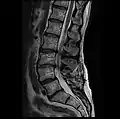

Graphic of lumbar laminectomy and two conditions it can address.

The lamina is a posterior arch of the vertebral bone lying between the spinous process (which juts out in the middle) and the more lateral pedicles and the transverse processes of each vertebra. The pair of laminae, along with the spinous process, make up the posterior wall of the bony spinal canal. Although the literal meaning of laminectomy is 'excision of the lamina', a conventional laminectomy in neurosurgery and orthopedics involves excision of the supraspinous ligament and some or all of the spinous process. Removal of these structures with an open technique requires disconnecting the many muscles of the back attached to them. A laminectomy performed as a minimal spinal surgery procedure is a tissue-preserving surgery that leaves more of the muscle intact and spares the spinal process. Another procedure, called the laminotomy, is the removal of a mid-portion of one lamina and may be done either with a conventional open technique or in a minimalistic fashion with the use of tubular retractors and endoscopes.

The reason for lamina removal is rarely, if ever, because the lamina itself is diseased; rather, it is done to break the continuity of the rigid ring of the spinal canal to allow the soft tissues within the canal to: 1) expand (decompress); 2) change the contour of the vertebral column; or 3) permit access to deeper tissue inside the spinal canal. A laminectomy is also the name of a spinal operation that conventionally includes the removal of one or both lamina, as well as other posterior supporting structures of the vertebral column, including ligaments and additional bone. The actual bone removal may be carried out with a variety of surgical tools, including drills, rongeurs and lasers.